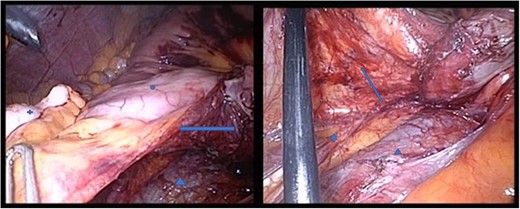

Both pictures display the hernia sac; in the right panel, the hernia sac has been elevated. Circle: terminal ileum, cross: appendix, star: ureter, triangle: V. cava, arrow: hernia sac, which has been opened